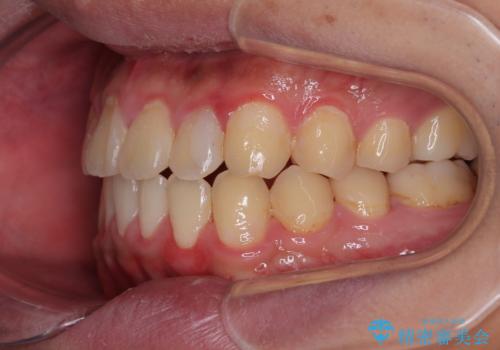

気になっていたクロスバイトは速やかに改善され、1年間で治療を終えることができました。

治療開始前は汚れが多く、全体的に歯肉が腫れていましたが、矯正治療を通して腫れも少しずつ改善されました。